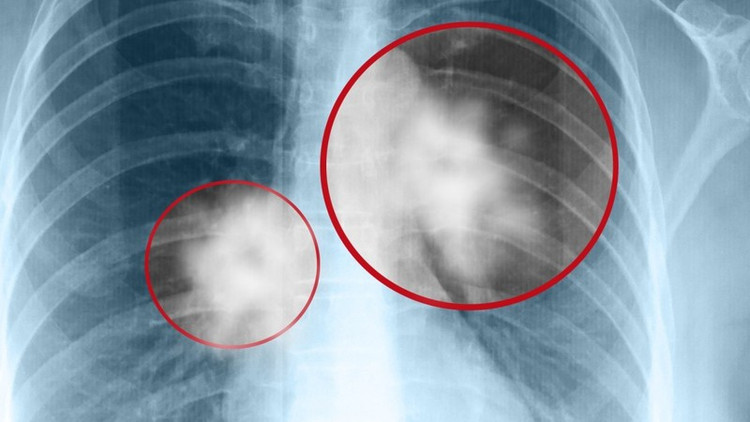

Có thể chẩn đoán viêm phổi do nấm bằng phương pháp chụp X quang. Ảnh minh họa/Nguồn internet